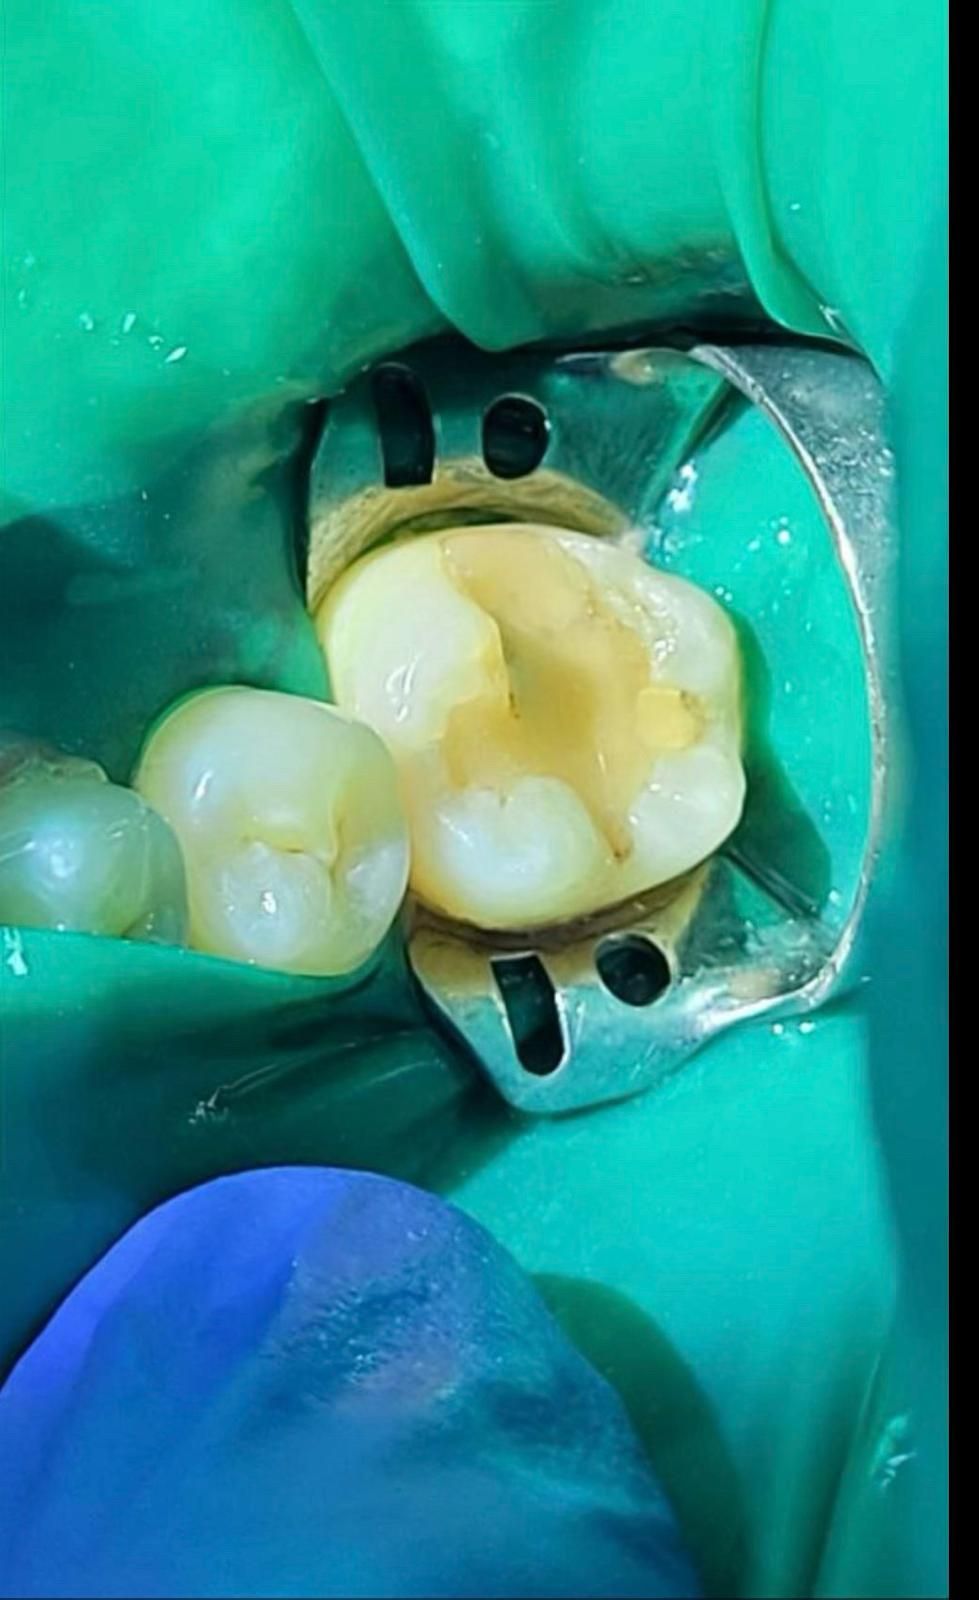

Zdjęcia i filmy